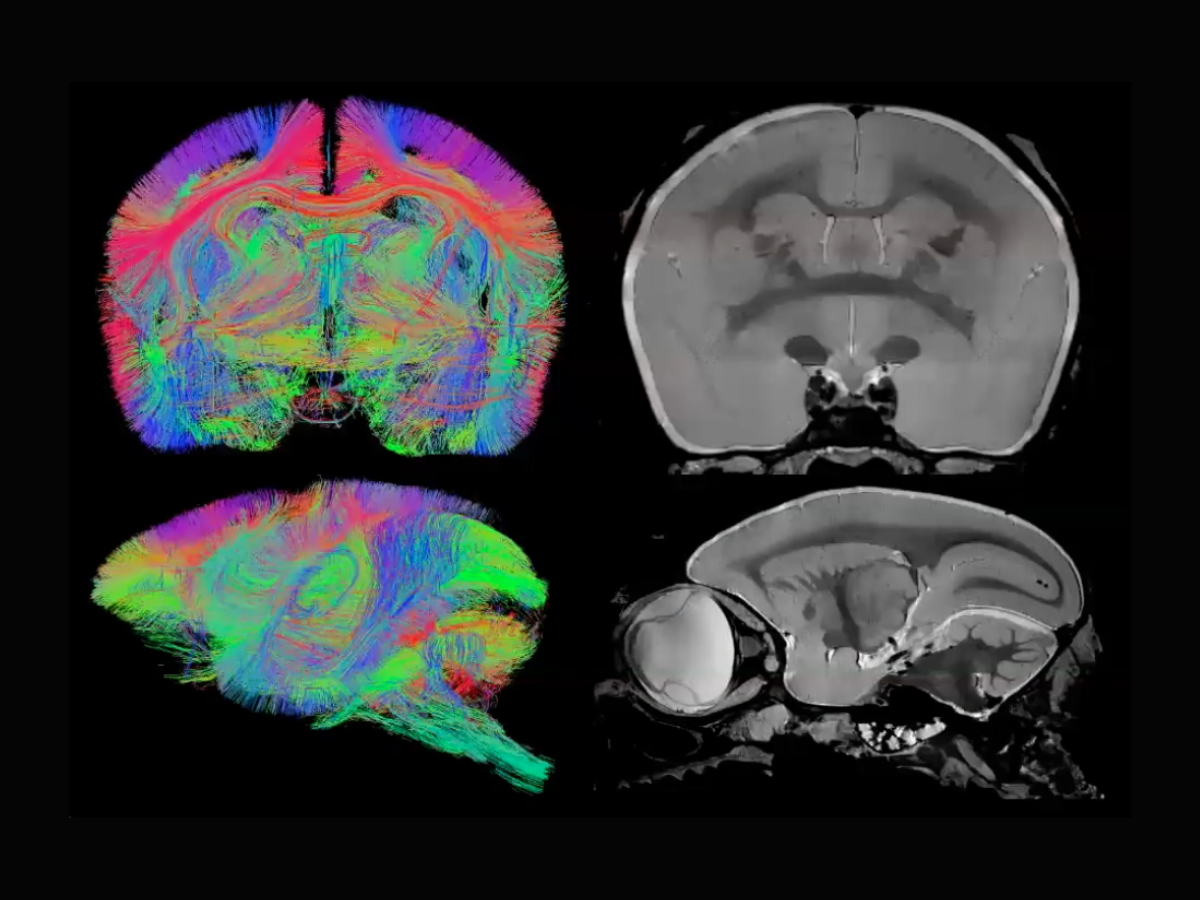

Exploring MRI's role in neuroscience research on model organisms Wu Neuroscience Model Organisms the genetic model organisms discussed in depth in the text—mus musculus (house. — in this review we will highlight the past and present techniques which have made, and continue to make, zebrafish an attractive model. — the model organism screening center (mosc) of the udn is a unique resource dedicated to utilizing informatics. — model organisms,. Neuroscience Model Organisms.

Exploring MRI's role in neuroscience research on model organisms Wu Neuroscience Model Organisms — by providing critical insights into these processes, decades of research using model organisms has been central. — model organisms, both common and unconventional, have been instrumental in uncovering basic principles of neural function. mit neuroscientists use a host of model organisms to study synaptic, neuronal and brain function, as well as to model. the genetic. Neuroscience Model Organisms.

Exploring MRI's role in neuroscience research on model organisms Wu Neuroscience Model Organisms — by providing critical insights into these processes, decades of research using model organisms has been central. the genetic model organisms discussed in depth in the text—mus musculus (house. — this issue combines insights from traditional models such as drosophila melanogaster and apis mellifera and. — the model organism screening center (mosc) of the udn is. Neuroscience Model Organisms.

Exploring MRI's role in neuroscience research on model organisms Wu Neuroscience Model Organisms — model organisms, both common and unconventional, have been instrumental in uncovering basic principles of neural function. — by providing critical insights into these processes, decades of research using model organisms has been central. The increasing diversity of model species currently employed in neuroscience broadens the scope of topics that can be conveniently and effectively explored. the. Neuroscience Model Organisms.